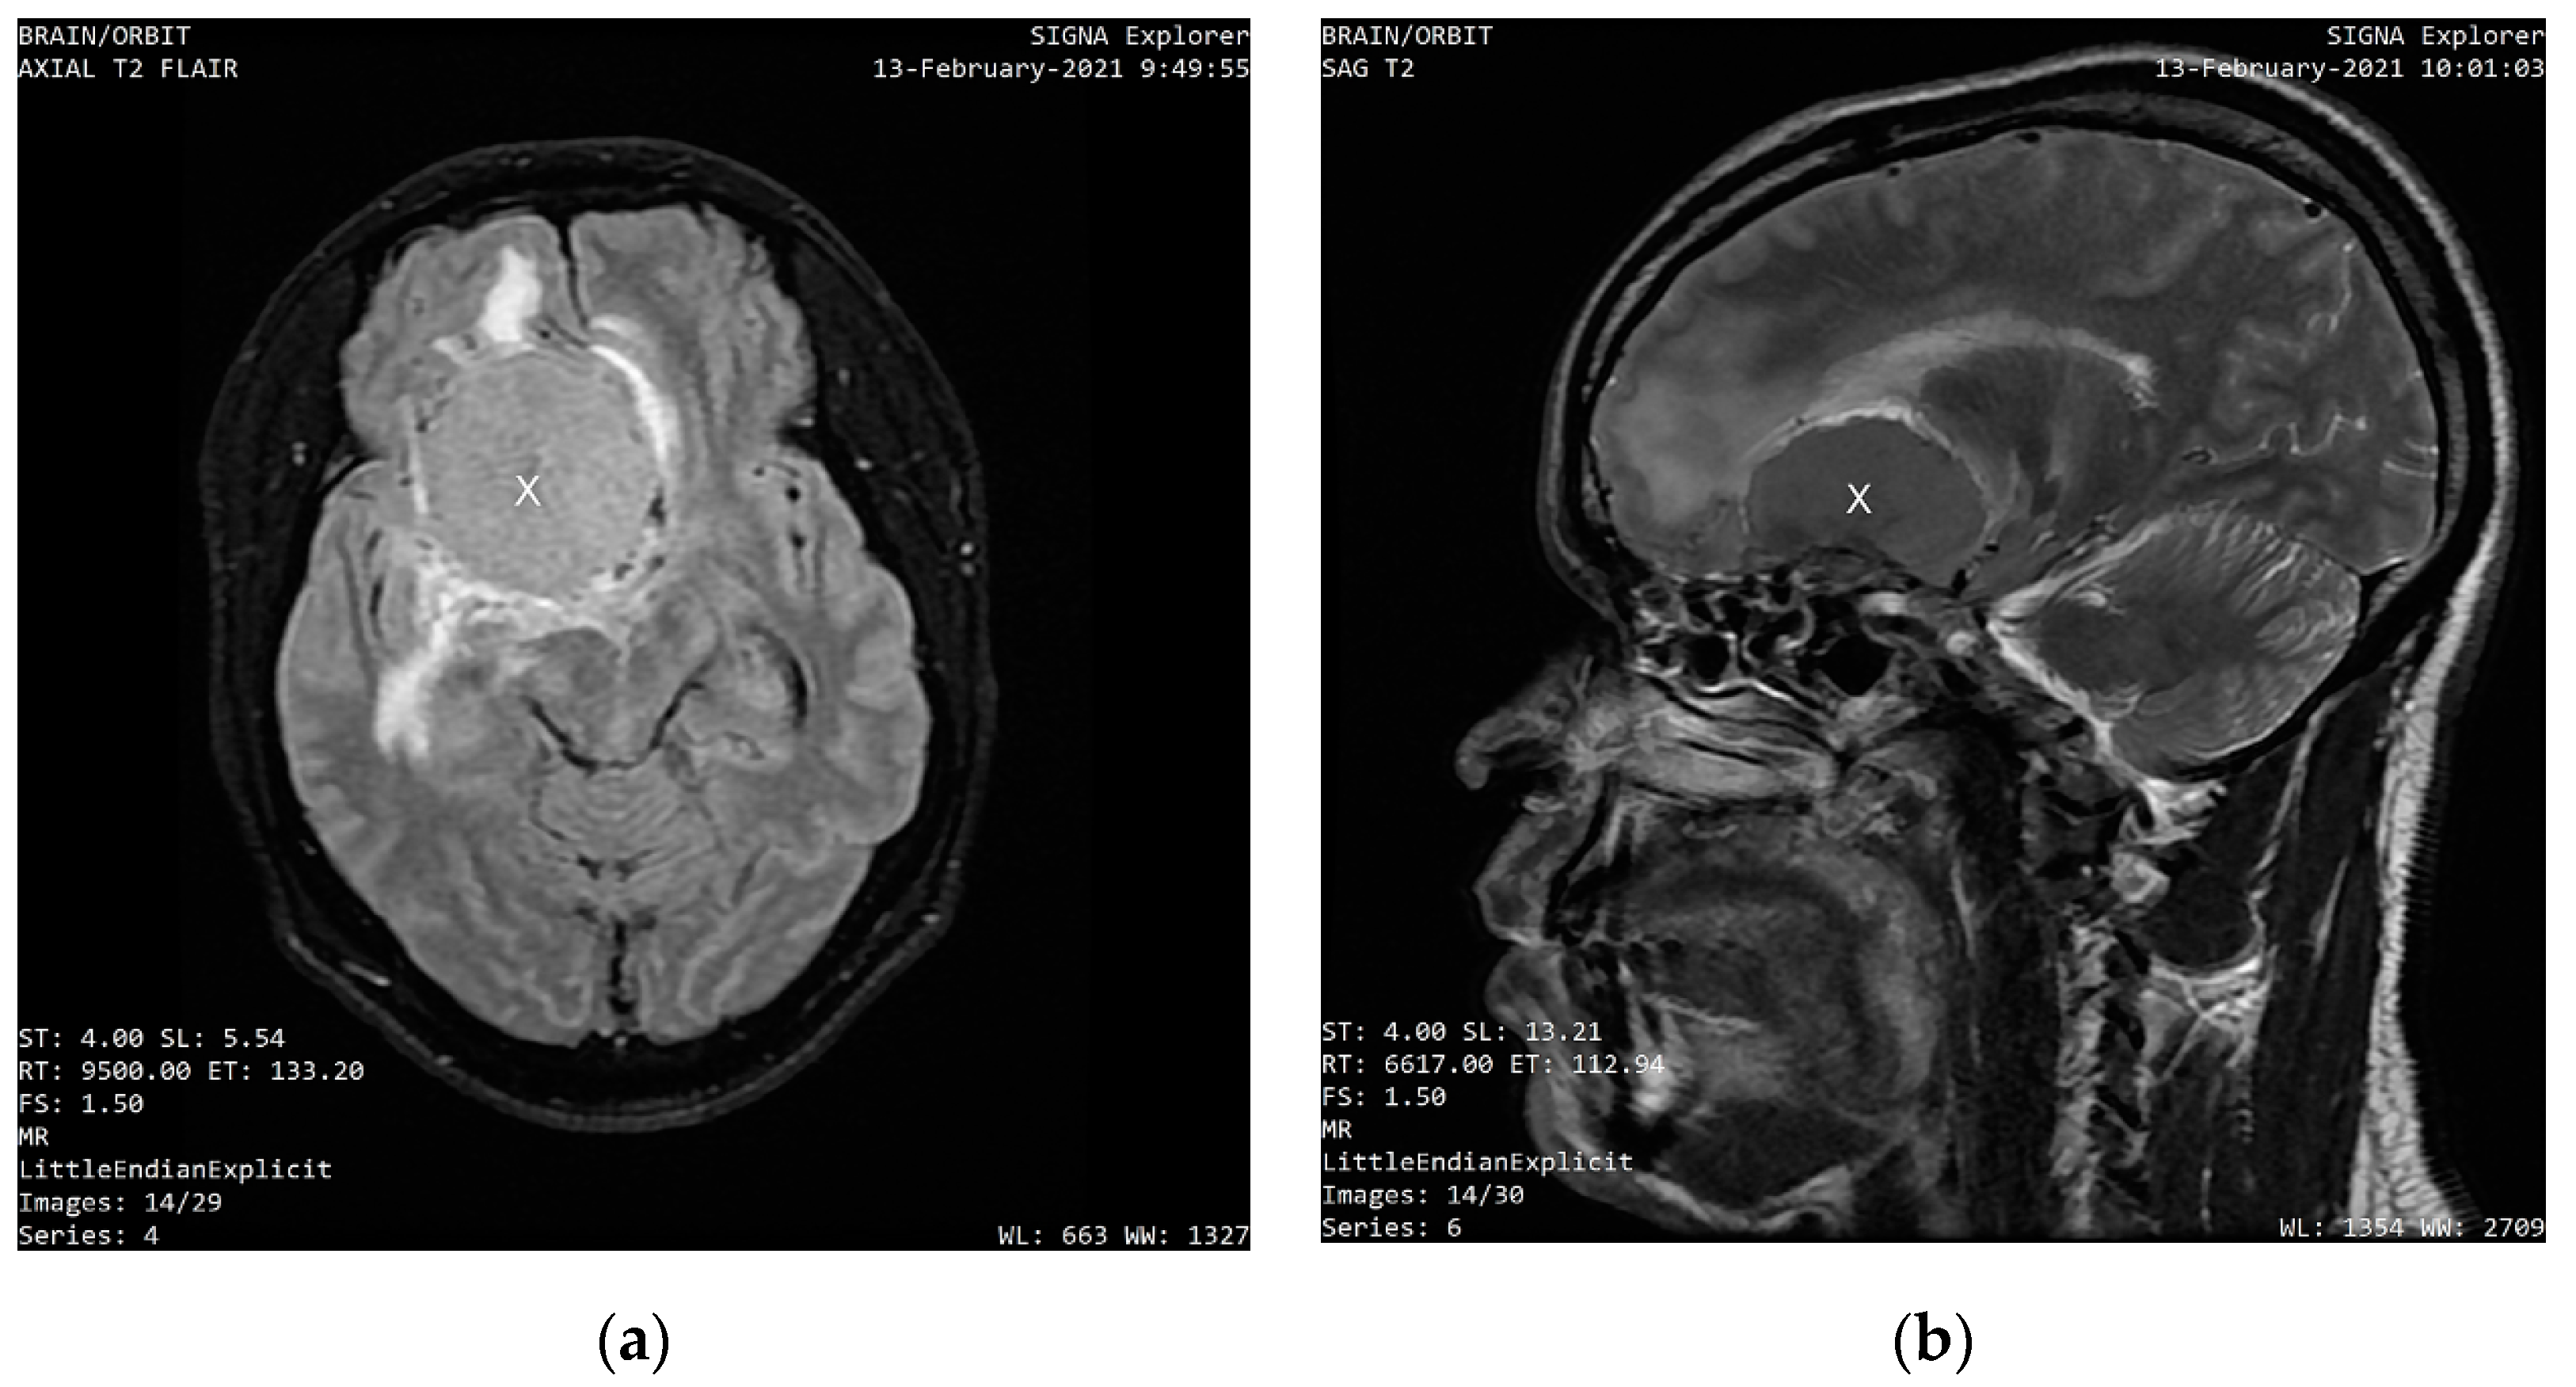

MRI scans, which were performed eight days after the first ophthalmologic examination on 13 February 2021, showed a uniformly enhancing base of skull mass lesion, consistent with a frontal-sphenoidal meningioma with a dimension of 4.6 cm × 3.5 cm × 4.9 cm (AP × L × TS). Figure 1 shows the axial and sagittal sections of the intracranial mass that compresses the right frontal lobe and displaces the falx.

Figure 1. (a) An axial section T2 weighted scan showing a well-circumscribed, homogenous mass compressing the right frontal lobe and displacing the falx and the left frontal lobe; (b) A sagittal section of the head of the same patient showing the compressive mass.